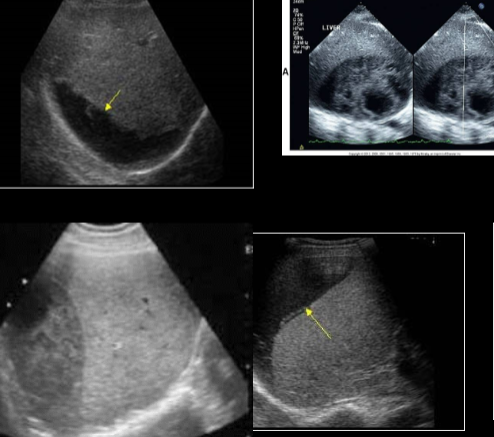

pyogenic abscess

ameobic abscess

echinococcal cyst

echinococcal cyst (squiggle lines is the water lily sign)